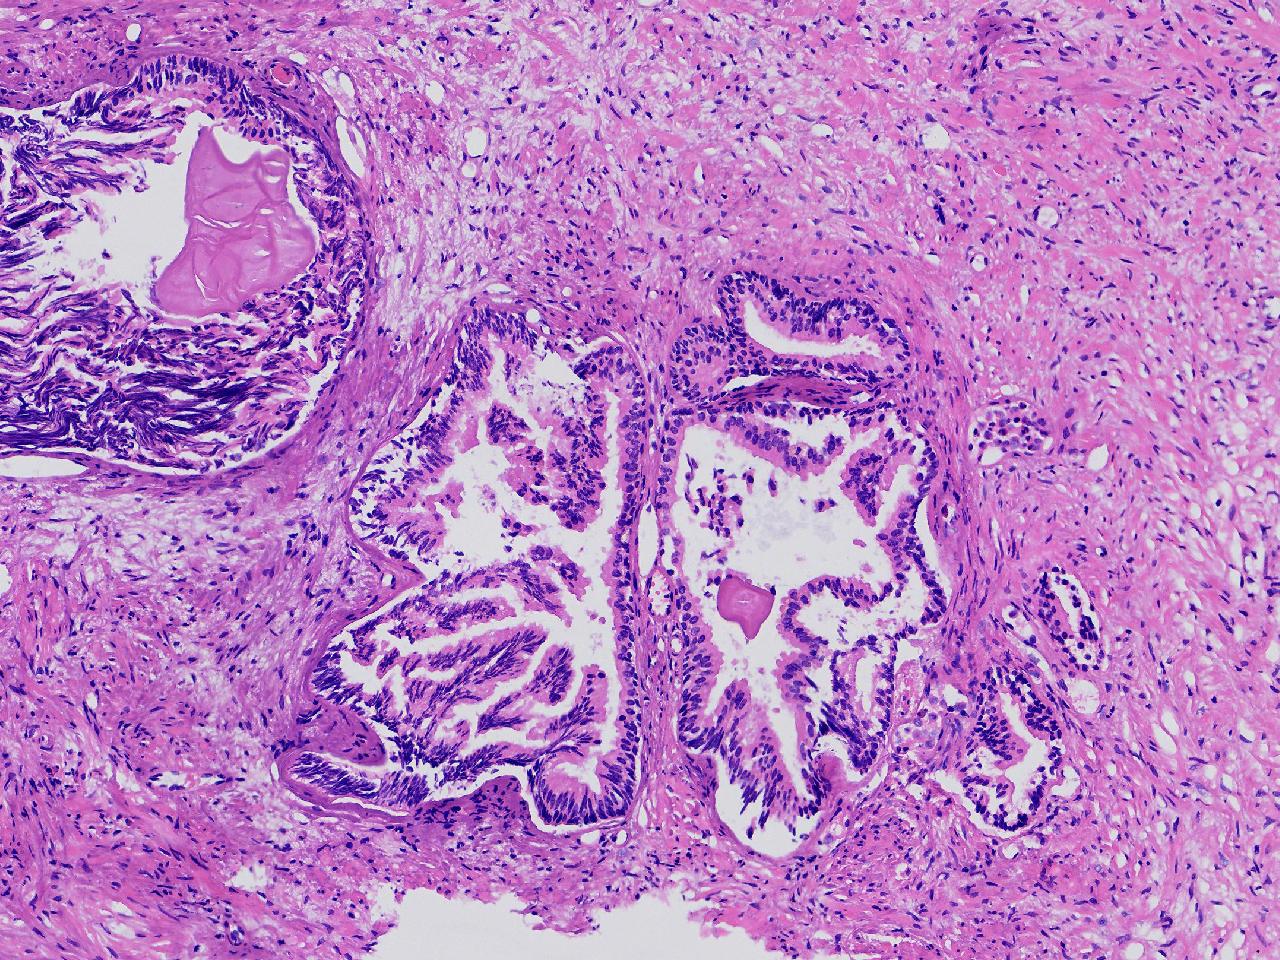

良性前列腺增生?

男,68岁,排尿困难半年余。行前列腺前切术。

前列腺电切标本

灰粉色条索状软组织多块,4X3X3厘米。

考虑为良性前列腺增生症

良性增生

BPH.